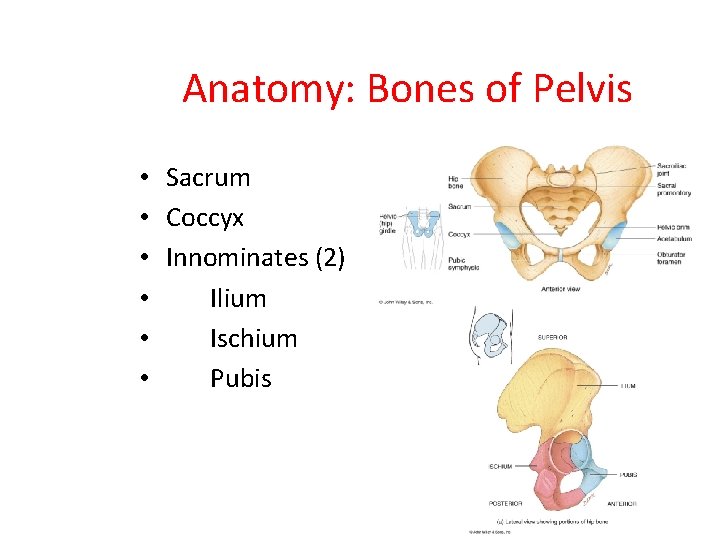

Anatomy: Bones of Pelvis • • • Sacrum Coccyx Innominates (2) Ilium Ischium Pubis